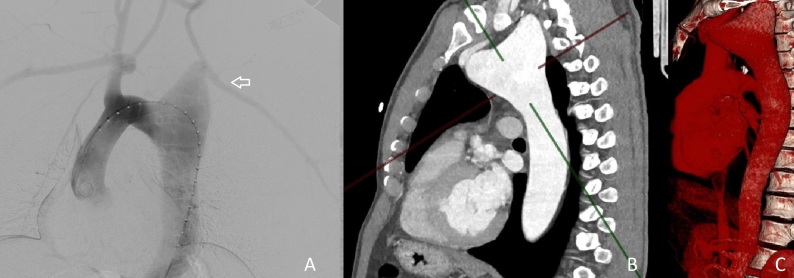

Aortic arch aneurysms are often asymptomatic, being diagnosed incidentally in tests such as computed tomography, magnetic resonance imaging, or echocardiogram. Conventional treatment involves thoracotomy surgery, although treatment can also be performed using endovascular techniques. This article presents a case report of a complex aneurysm of the aortic arch with involvement of the left subclavian artery. Treatment was initiated with debranching of the supra-aortic trunks by carotid-carotid and carotid-subclavian bypasses, followed by ligation of the common carotid and left subclavian arteries. A second procedure was then needed to construct a surgical vascular conduit using a Dacron graft to obtain access to the aortic arch for the stent graft delivery device, due to the narrow caliber of the external femoral and iliac arteries. This report illustrates a satisfactory outcome in a case of aortic arch aneurysm with complex anatomy.